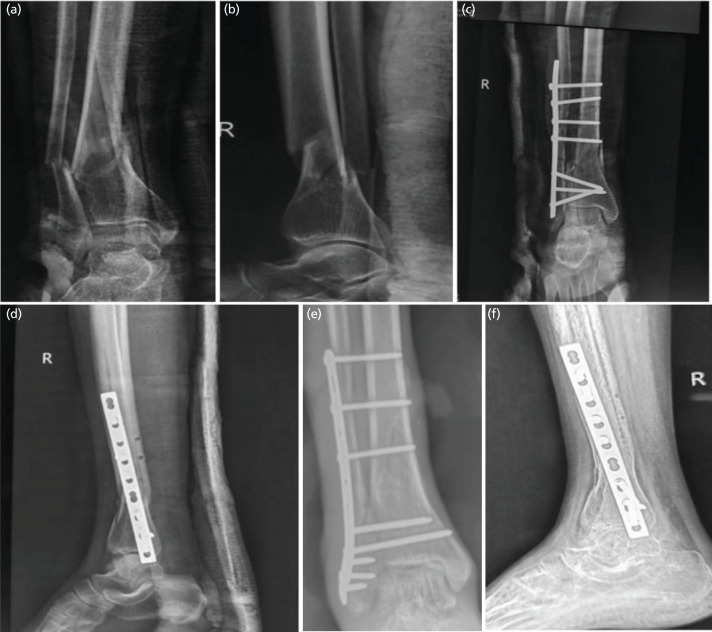

Introduction: Despite recent advances, management of distal tibial fractures is challenging, with high rate of complications. Fibula pro tibia plating technique fixes fibula and tibia together, via laterally placed fibular plate without disturbing the tibial soft tissue sleeve. We contemplated this pilot study to assess effectiveness of fibula pro tibia plating in management of distal tibia fibula fractures.

Materials and methods: A total of 30 patients with distal tibia fibula fractures with fracture line extending within 5cm from tibial plafond were managed with fibula pro tibia plating, with or without minimal articular fixation. Outcome evaluation was done by union, union time, alignment and functional outcome as assessed by AOFAS score.

Results: Mean age in the series was 39.4 years with male to female ratio of 3:2. Mean duration of surgery, blood loss and C arm exposure were 79 minutes (range 52 to 98min), 80ml (range 62 to 102ml) and 48 shoots (range 36 to 81 shoots), respectively. All fractures united in mean union time of 10.2 weeks (range 9 to 14 weeks) with acceptable alignment in all the patients except one. Mean AOFAS score was 86.3 (range 70 to 93) with 29 patients having good to excellent outcome. One patient had varus malunion and in one case infection was seen.

Conclusion: Fibula pro tibia plating can be successfully used to manage complex distal tibia fractures which leaves the soft tissue and periosteal sleeve undisturbed, thus avoiding wound related problems and leading to early union.